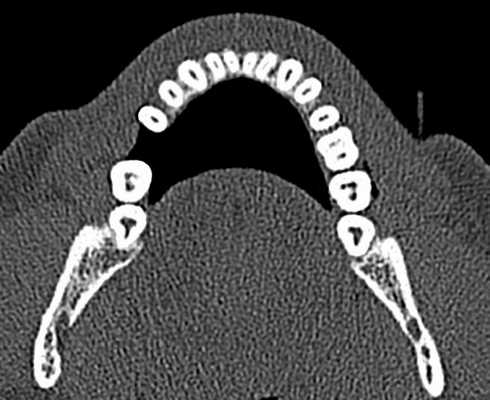

Описание рентгенологического исследования 4.6, 4.7 зубов в динамике. 4.6 зуб депульпирован. Коронковая часть восстановлена пломбой. Краевое прилегание не нарушено. Строение канально-корневой системы: 2 корня, 5 каналов. Все каналы заполнены пломбировочным материалом плотно, на всем протяжении. Пространство периодонтальной связки и периапикальные ткани не изменены. Твердая пластинка альвеолы прослеживается на всем протяжении (рис. 8, 9) .

Рис. 8. КЛКТ, МПР. Оценка качества обтурации каналов мезиального корня 4.6 зуба.

Рис. 9. КЛКТ, МПР. Оценка качества обтурации каналов дистального корня 4.6 зуба.

4.7 зуб депульпирован. Коронковая часть восстановлена пломбой. Краевое прилегание не нарушено. Строение канально-корневой системы: 2 корня, 5 каналов. Все каналы запломбированы гомогенно, полностью. Сохраняется краевая апикальная резорбция дистального корня. Наблюдается практически полная регенерация очага деструкции в проекции верхушек обоих корней. Имеется остаточное расширение апикального периодонта в области дистального апекса (рис. 10, 11) .

Рис. 10. КЛКТ. МПР. Оценка качества обтурации каналов мезиального корня 4.7 зуба и состояния периапикальных тканей.

Рис. 11. КЛКТ. МПР. Оценка качества обтурации каналов дистального корня 4.7 зуба и состояния периапикальных тканей.